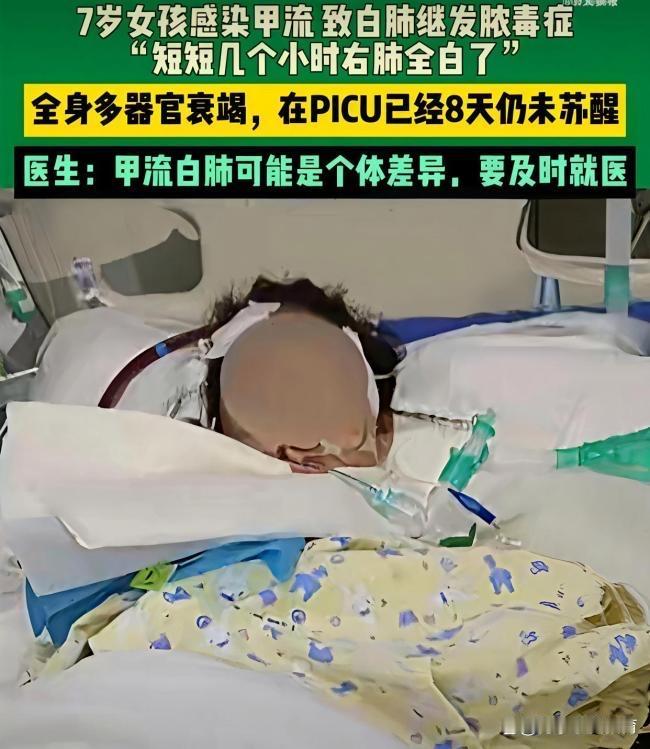

宝妈们警惕❗️郑州7岁女孩甲流几小时右肺全白 河南郑州7岁女孩感染甲流后,几小时内右肺全白,合并细菌感染引发脓毒症及多脏器衰竭,在PICU救治8天仍未苏醒,这则消息令人揪心,更敲响了流感防控的警钟。 甲流绝非普通感冒,尤其对儿童群体而言,病毒侵袭后可能快速进展。儿童免疫系统尚未完善,感染甲流后易出现重症,病毒会破坏呼吸道黏膜防御,让细菌有机可乘,进而引发肺炎、脓毒症等凶险并发症,从发病到重症可能仅需数小时,脓毒症死亡率高达30%-50%,延误治疗每小时都会增加风险。 不少家长存在认知误区,将流感等同于普通感冒,忽视检查与及时干预。实则儿童出现持续高热、呼吸急促、精神萎靡等症状,需立即就医,完善血常规、CRP等检查排查合并感染,尽早用抗病毒药物阻断病情进展。当前流感高发季,家长需摒弃侥幸心理,做好防护的同时,警惕重症信号,早发现、早治疗才是守护孩子健康的关键。